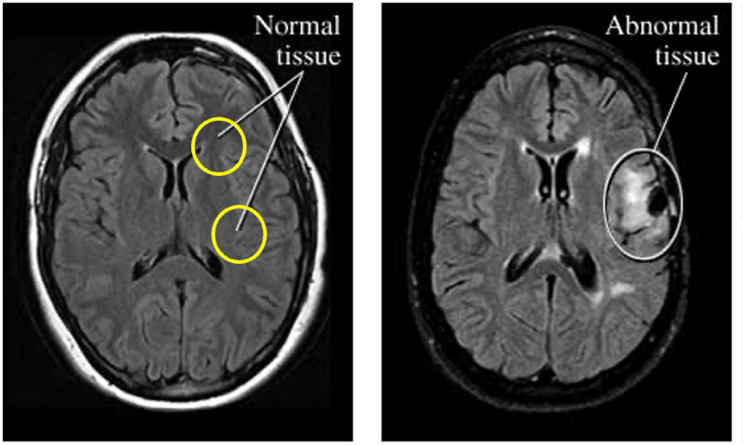

Conventional MRI distinguishes MRI-positive epilepsy (visible abnormalities like focal cortical dysplasia (FCD)) from MRI-negative epilepsy, where scans appear normal despite persistent seizures. This diagnostic gap underscores the need for quantitative imaging to detect subtle cortical changes invisible to standard radiology.

MRI features of FCD II are subtle but critical for diagnosis as Figure 4 demonstrates.